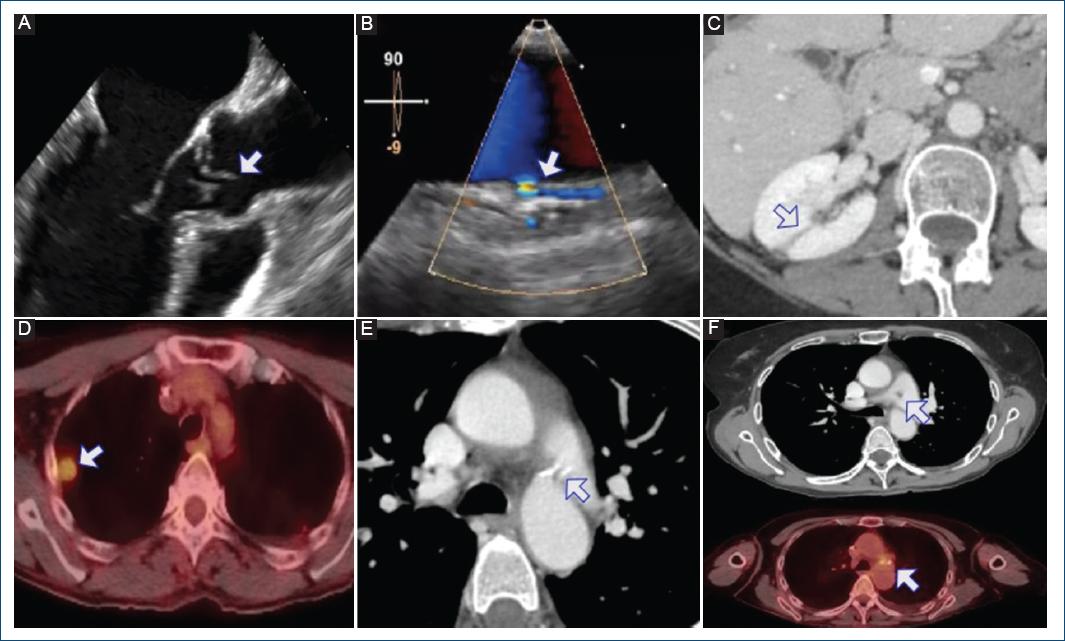

Tres hemocultivos resultaron positivos para Staphylococcus aureus sensible a meticilina y se inició antibioterapia con cefazolina y linezolid. El ecocardiograma mostró una insuficiencia aórtica moderada por prolapso de la cúspide coronaria derecha con una vegetación adherida de 5 mm (Fig. 1A), junto con un cortocircuito de izquierda a derecha entre la aorta descendente y la rama izquierda de la arteria pulmonar sugestivo de ductus arterioso permeable (DAP) (Fig. 1B). No se observaron hallazgos sugestivos de endocarditis derecha.

Figura 1 Endocarditis aórtica complicada con endarteritis de ductus arterioso permeable (DAP), embolias sépticas sistémicas y pulmonares. A: prolapso de cúspide coronaria derecha con vegetación adherida de 5 mm. B: cortocircuito izquierda-derecha, sugestivo de DAP. C: embolias sépticas sistémicas (riñón derecho). D: embolias sépticas pulmonares bilaterales. E: DAP. F: vegetación en el lado pulmonar del DAP.

Un estudio con tomografía por emisión de positrones-tomografía computarizada (PET-TC) completo reveló la presencia de embolias sépticas sistémicas (riñón derecho, Fig. 1C) y pulmonares bilaterales (Fig. 1D). Se confirmó el hallazgo previo de DAP y se observó una nueva vegetación en el lado pulmonar del DAP (Figs. 1E y F).